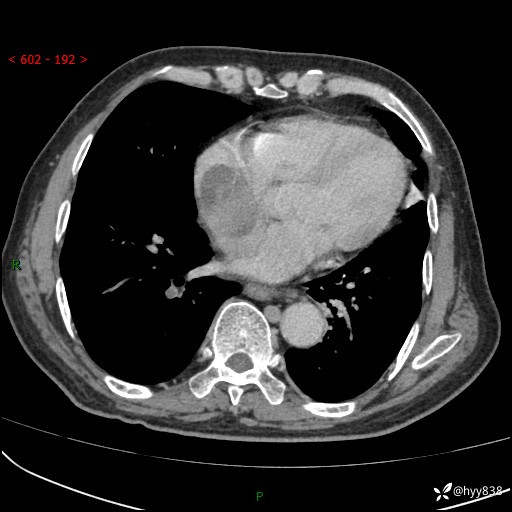

主诉:检查发现心脏肿物1周余。

现病史:患者一周余前因腹胀就诊我院消化科门诊,查心脏彩超提示右房内异常回声(粘液瘤?),无明显心慌、气喘、胸闷,无明显胸痛、咳嗽咳痰等不适,活动量增加后出现心慌、气喘不适。现为求进一步治疗,就诊我科,门诊遂以“心脏肿物”收入院。 自发病以来,精神睡眠一般,食欲尚可,大小便正常,体力下降,体重无明显变化。

胸部CT平扫+增强